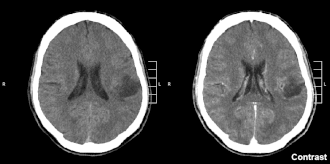

L'imagerie par résonance magnétique (IRM) est l'examen de référence, plus sensible et spécifique que le scanner crânien pour les tumeurs cérébrales[29], les séquences T2 et Flair permettent d’évaluer au mieux l’extension de la tumeur et de l’œdème péri tumoral (envahie par les cellules tumorales le plus souvent). L'image caractéristique est une masse fixant le gadolinium (produit de contraste pour l'IRM) avec une nécrose centrale et un œdème péritumoral.